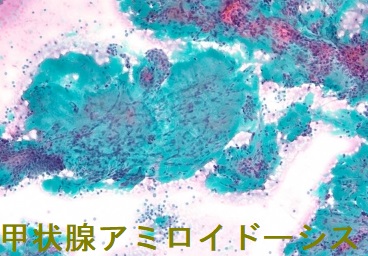

甲状腺アミロイドーシスの細胞診

甲状腺アミロイドーシスの細胞診では通常、写真のように無構造好酸性物質を認め、その中に線維芽細胞が増生しています。濾胞組織は破壊され、細胞成分は少ない。

また、多核巨細胞と少数の類上皮細胞を認め、亜急性甲状腺が疑われた報告例があります。(第61回 日本甲状腺学会 O31-5 細胞診で亜急性甲状腺炎が疑われたアミロイド甲状腺腫の1例)(亜急性甲状腺炎様症候群)